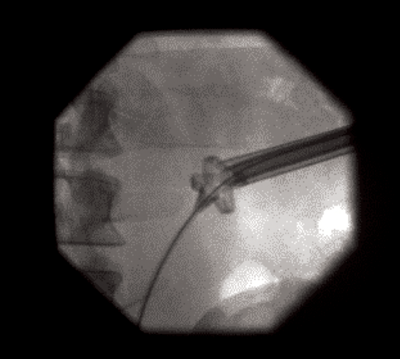

The lower ureter was tortuous and of the ‘fish-hook’ type. A nephrostogram revealed a stricture at the vesicoureteric junction (VUJ) and incision of the VUJ using a Collins knife failed to demonstrate the lumen (Figure 2 and 3).

Figure 2.

Figure 3.